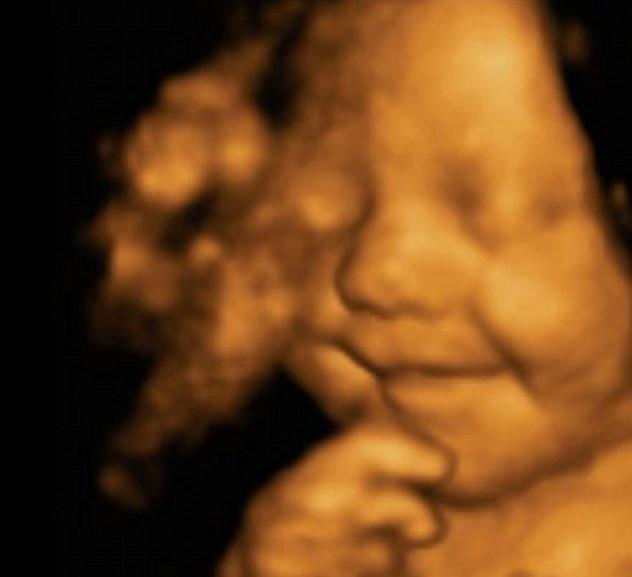

4D scan Leo Hargreaves Diambil Sebelum 31 Minggu Dalam Kandungan Ibunya

Ibunya Amy Cregg mengatakan, “ Saya dan suami saya mitra Leighton benar-benar terkejut, bahkan dokter yang mengecek kandungan saya kagum ketika melihat wajah bayi saya.”

Jaman sekarang, teknologi semakin canggih. Dengan melakukan scan 4D, calon orang tua dapat melihat sekilas tentang bagaimana anak mereka akan terlihat. Dengan Scanner 4D, mesin ini akan mengambil gambar dari berbagai sudut untuk membuat gambar tiga dimensi yang jelas.

Scan 4D adalah salah satu teknologi canggih dari USG tradisional di mana gelombang suara frekuensi sangat tinggi yang digunakan untuk menghasilkan gambar dari apa yang ada dalam tubuh . Seperti bentuk-bentuk yang lebih tua dari ultra- suara , gelombang suara yang dipancarkan dan ditempatkan pada perut ibu yang dapat melihat daerah di dalam rahim .

Scan 4D menggunakan frekuensi yang sama dari gelombang suara seperti pada USG normal. Tapi gelombang suara yang diarahkan dari banyak sudut , menghasilkan ' waktu yang tepat ' video janin ketika bergerak dan memungkinkan para ilmuwan untuk mengatakan gambar dalam empat dimensi .

Seorang juru bicara perusahaan yang melakukan scan , USG Babybond Ultrasound di Burnley , mengatakan: " petugas yang mengscan mencoba memakai mesin 4D yang lain kaget, karena bayi imut Amy ini tetap tersenyum saat di scan.

Menurutnya “ bayi Leo merupakan bayi yang selalu tersenyum yang pernah kami lihat ”.